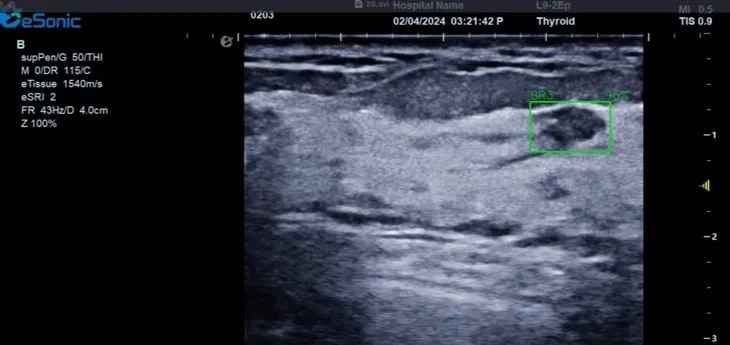

新航娱乐医疗(ESI)表示,其最新的人工智能功能可以帮助到医疗机构的工作效率,功能包括,实时、动态、快速自动识别病灶,良恶性病灶概率预测,甲状腺结节和乳腺的二维灰阶动态自动实时检测需求,提供多个结节动态检测轮廓框。实时获取多幅具备临床特征(大小、属性等)的结节切面,同时提供当前切面所示结节的结节大小、属性特征、TI-RADS 分级。

对于甲状腺结节相关的自动检测功能,甲状腺结节病灶检出率≥95%,良恶性分类灵敏度≥90%、良恶性分类特异度≥85%。